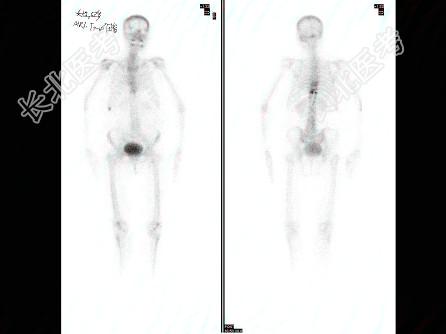

- 多项选择题女性,62岁, 诉腰背痛1月余,行

Tc

-MDP骨显像如图, 可能的诊断是 ( )

A、胸10为新发的骨折

B、胸7~10椎体压缩性骨折

C、肋骨圆点状浓聚亦可能为骨折

D、骨质疏松征象

E、胸7~9陈旧性骨折